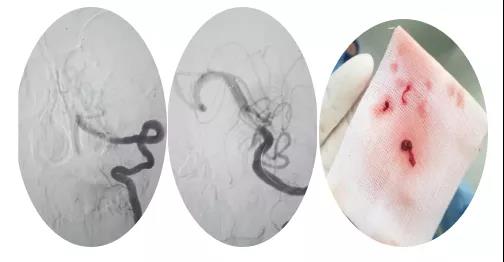

18:30手術(shù)開始,造影為基底動(dòng)脈閉塞,與患者家屬充分溝通,患者家屬同意給予介入取栓治療。共取栓2次,取出少量暗紅色血栓塊。造影示:基底動(dòng)脈有重度狹窄,結(jié)合患者病情演變及造影結(jié)果,考慮為動(dòng)脈粥樣硬化性狹窄。根據(jù)患者造影結(jié)果,目前單純?nèi)∷o法達(dá)到預(yù)期效果,決定給予基底動(dòng)脈支架植入術(shù)。根據(jù)患者基底動(dòng)脈直徑選擇3.0*13mm apollo球擴(kuò)支架,支架植入后造影示狹窄消失。

支架植入后患者神志轉(zhuǎn)清,四肢均可活動(dòng),左側(cè)肢體活動(dòng)略差于右側(cè),收入神經(jīng)內(nèi)四科病房進(jìn)一步治療。術(shù)后第三天患者神志清,四肢活動(dòng)基本正常,住院5天轉(zhuǎn)入當(dāng)?shù)蒯t(yī)院治療。?